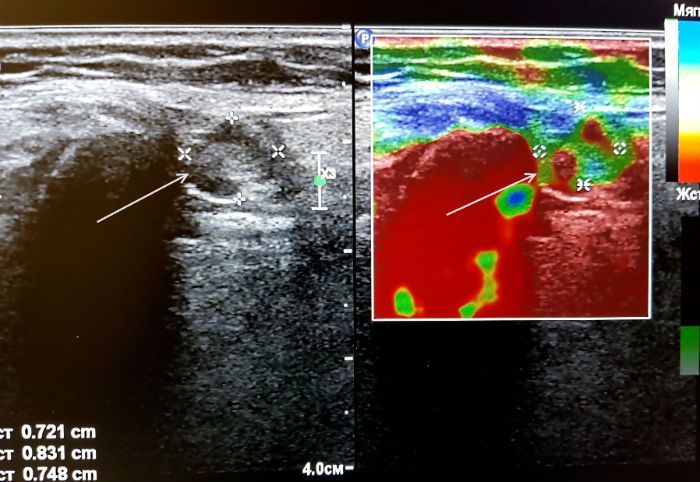

Исследование мягких тканей и подкожной клетчатки

Эластография – это прекрасное дополнение к классическому ультразвуковому способу исследования мягких тканей и подкожной клетчатки. Сегодня УЗ-технологии активно используют для мониторинга кожных отеков и заживления ран, для изучения структуры кожи при таких заболеваниях, как псориаз, склеродермия, панникулит. С помощью эластографии стало возможным быстрое выявление опухолевых образований (меланома, базальноклеточная карцинома, сквамозноклеточная карцинома).

Показания к проведению эластографии мягких тканей:

• наличие пальпаторно определяемого инфильтрата для уточнения природы этого образования;

• выявление непальпируемого образования, не имеющего четких границ;

• проведение дифдиагноза между воспалением, липомой, первичным раком кожи или метастазами;

• оценка состояния регионарных лимфатических узлов.

ЛимфаденопатияЛимфаденопатия